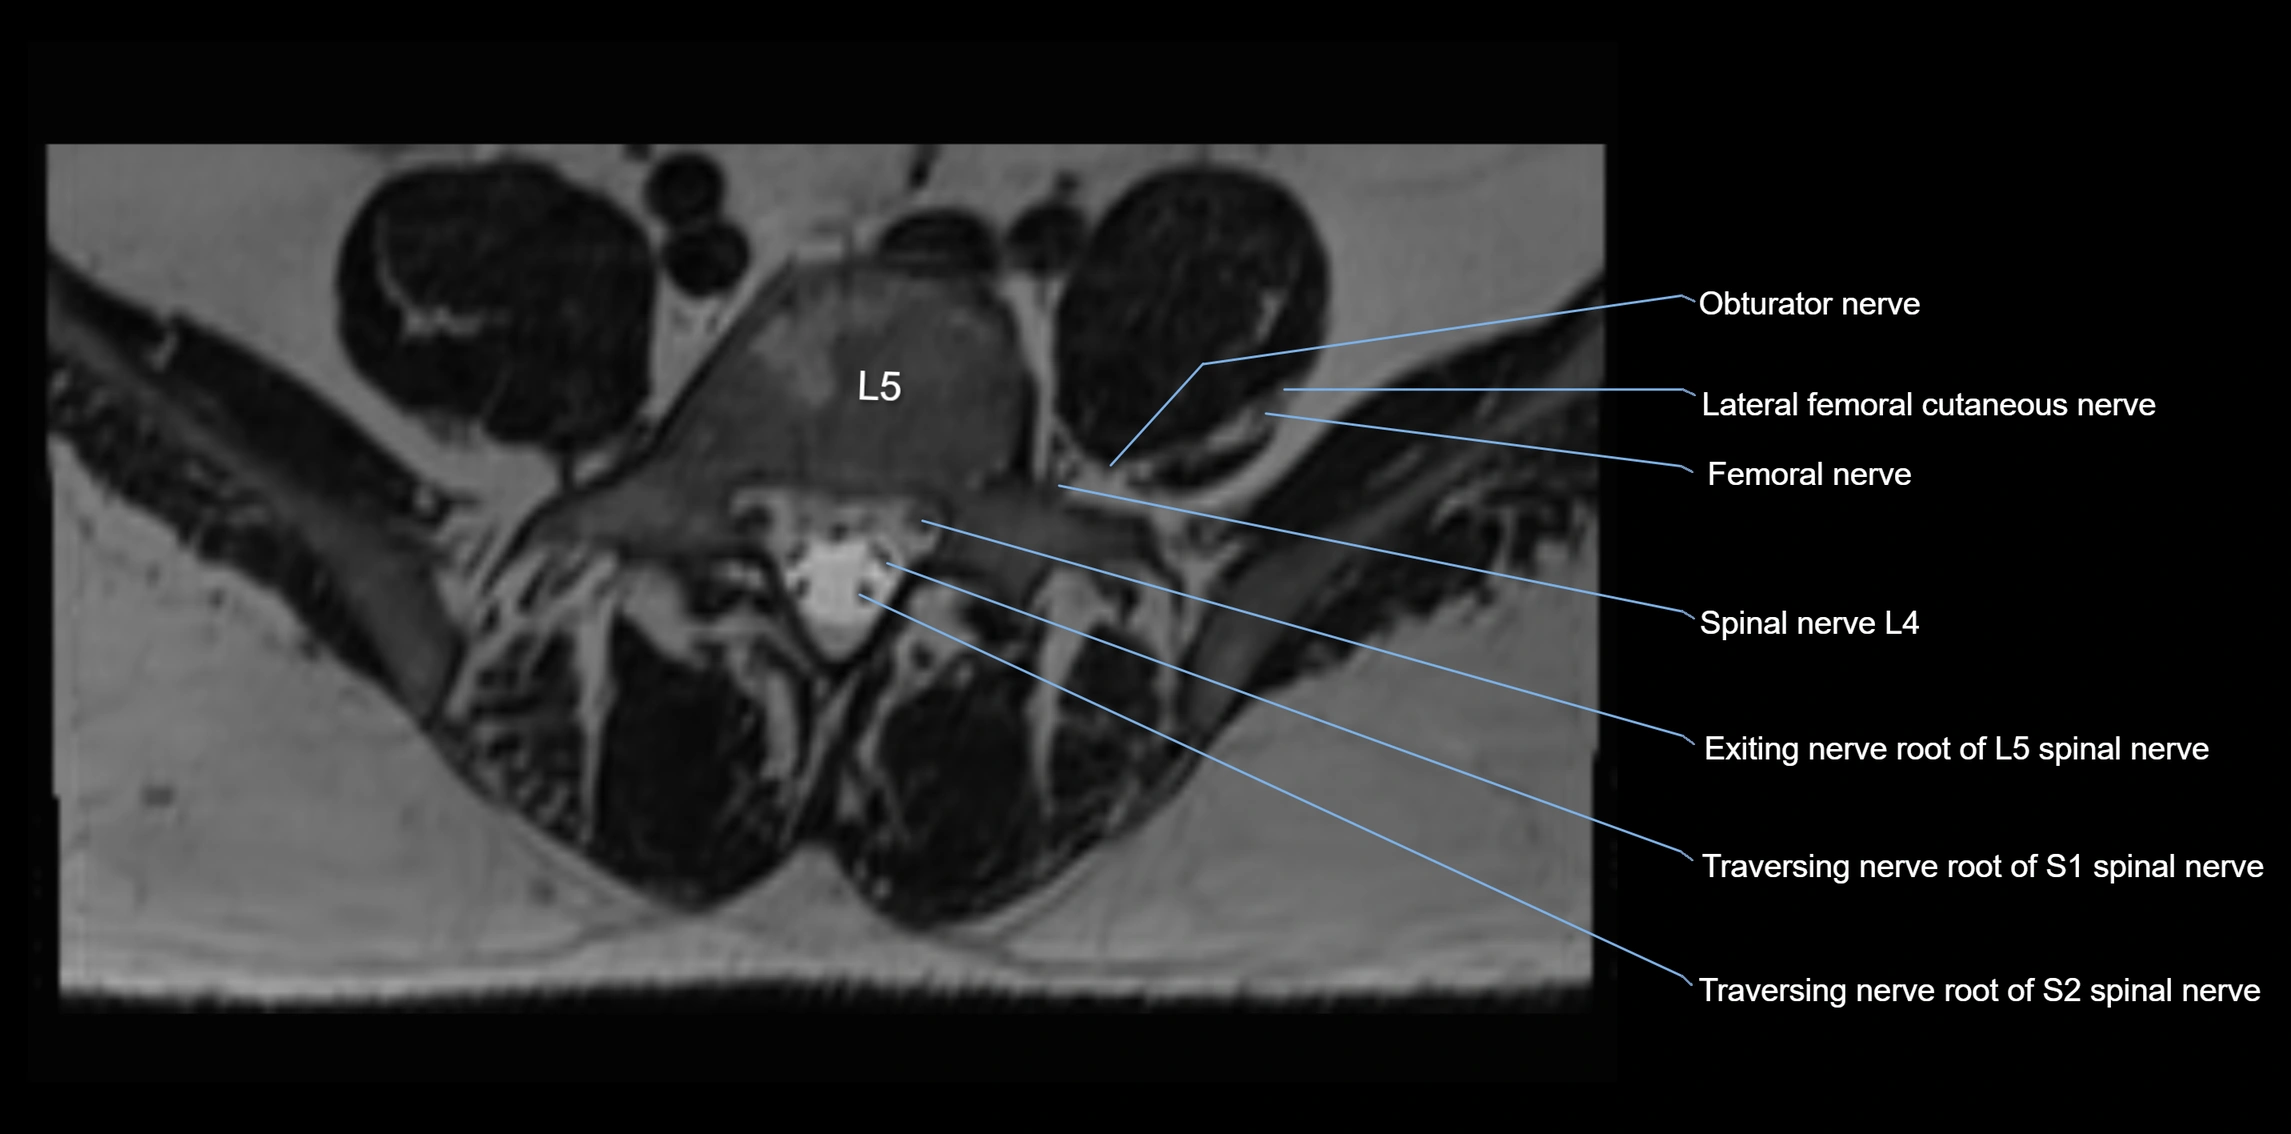

MRI Appearance

T1-weighted images:

• Nerve appears as a very thin low-to-intermediate signal intensity structure

• Surrounded by bright fat, aiding visualization

T2-weighted images:

• Nerve shows intermediate to mildly hyperintense signal compared to muscle

• Pathological involvement appears brighter

STIR (Short Tau Inversion Recovery):

• Normal nerve appears dark

• Inflamed or entrapped nerve appears bright hyperintense

T1 Fat-Sat Post-Contrast:

• Normal nerve enhances minimally

• Pathologic nerve (neuritis, entrapment, tumor infiltration) shows focal or diffuse enhancement

3D T2 SPACE / CISS:

• Nerve appears intermediate to mildly hyperintense compared to muscle

• Surrounded by bright fat or CSF, improving visualization

• Best sequence for mapping small pelvic nerves such as the anococcygeal